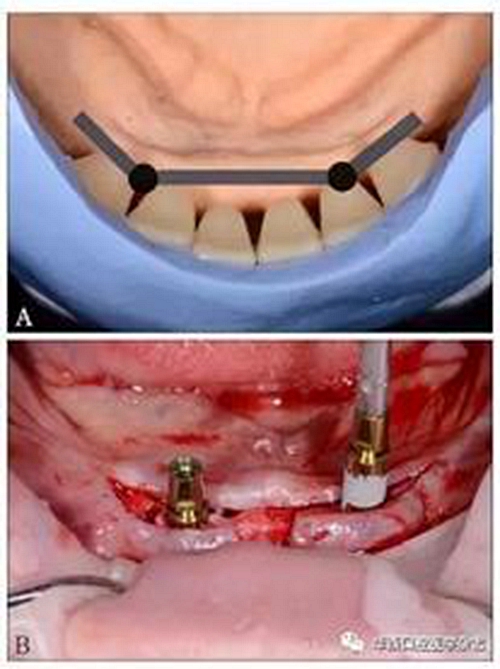

(3)制定治療計(jì)劃:黏膜支持式總義齒修復(fù)上頜無牙頜;種植體-桿卡固位覆蓋義齒修復(fù)下頜無牙頜。根據(jù)人工牙的排列設(shè)計(jì)桿的位置,使桿位于牙槽嵴與人工牙間,并設(shè)計(jì)種植位點(diǎn)(圖3A);運(yùn)用雙側(cè)游離端短懸臂,增加義齒穩(wěn)定與固位[9,13]。依診斷排牙翻制種植手術(shù)導(dǎo)板。

(4)種植手術(shù):依據(jù)種植手術(shù)導(dǎo)板,在下頜雙側(cè)側(cè)切牙與尖牙之間的位點(diǎn)各植入1枚3.8 mm×11 mm種植體(XIVE,F(xiàn)riadent公司,德國),植入扭矩25 N·cm(圖3B)。